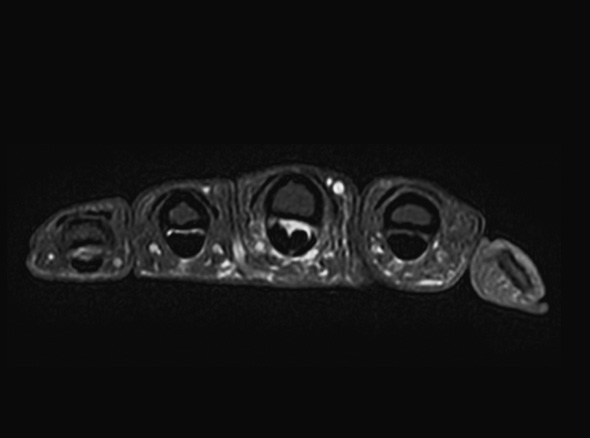

학술적으로는 협착성 굴곡건염이라고 표현하고, A1 활차라는 터널에 굽히는 힘줄이 마찰되다가 힘줄의 내부적인

변화가 일어나 병이 생긴 상태를 의미합니다. 내부적인 변화가 심해질 경우 힘줄이 부어 결절을 이룰 수도 있는데

이러한 경우 A1 활차에 끼어서 딸깍 거리거나 걸려서 안 펴지는 증상이 생깁니다.